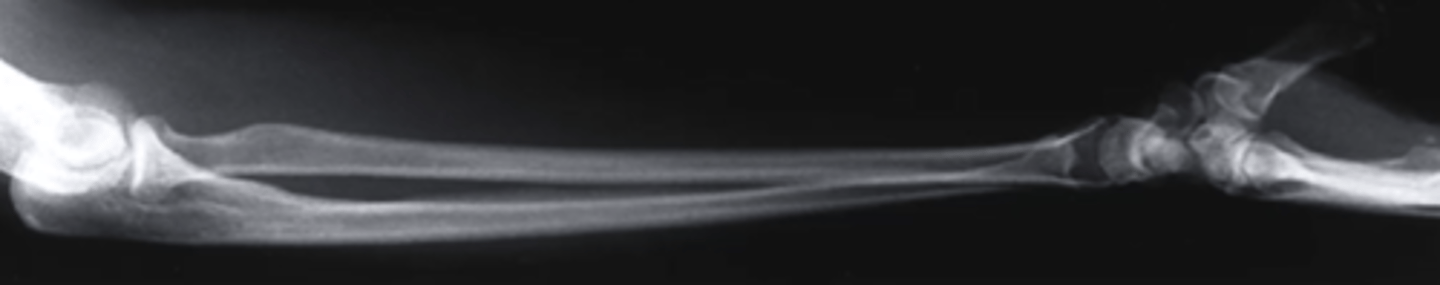

lateral forearm

what view is this

olecranon process

what does this pink line point to?

ulna

radius

radiocarpal joint